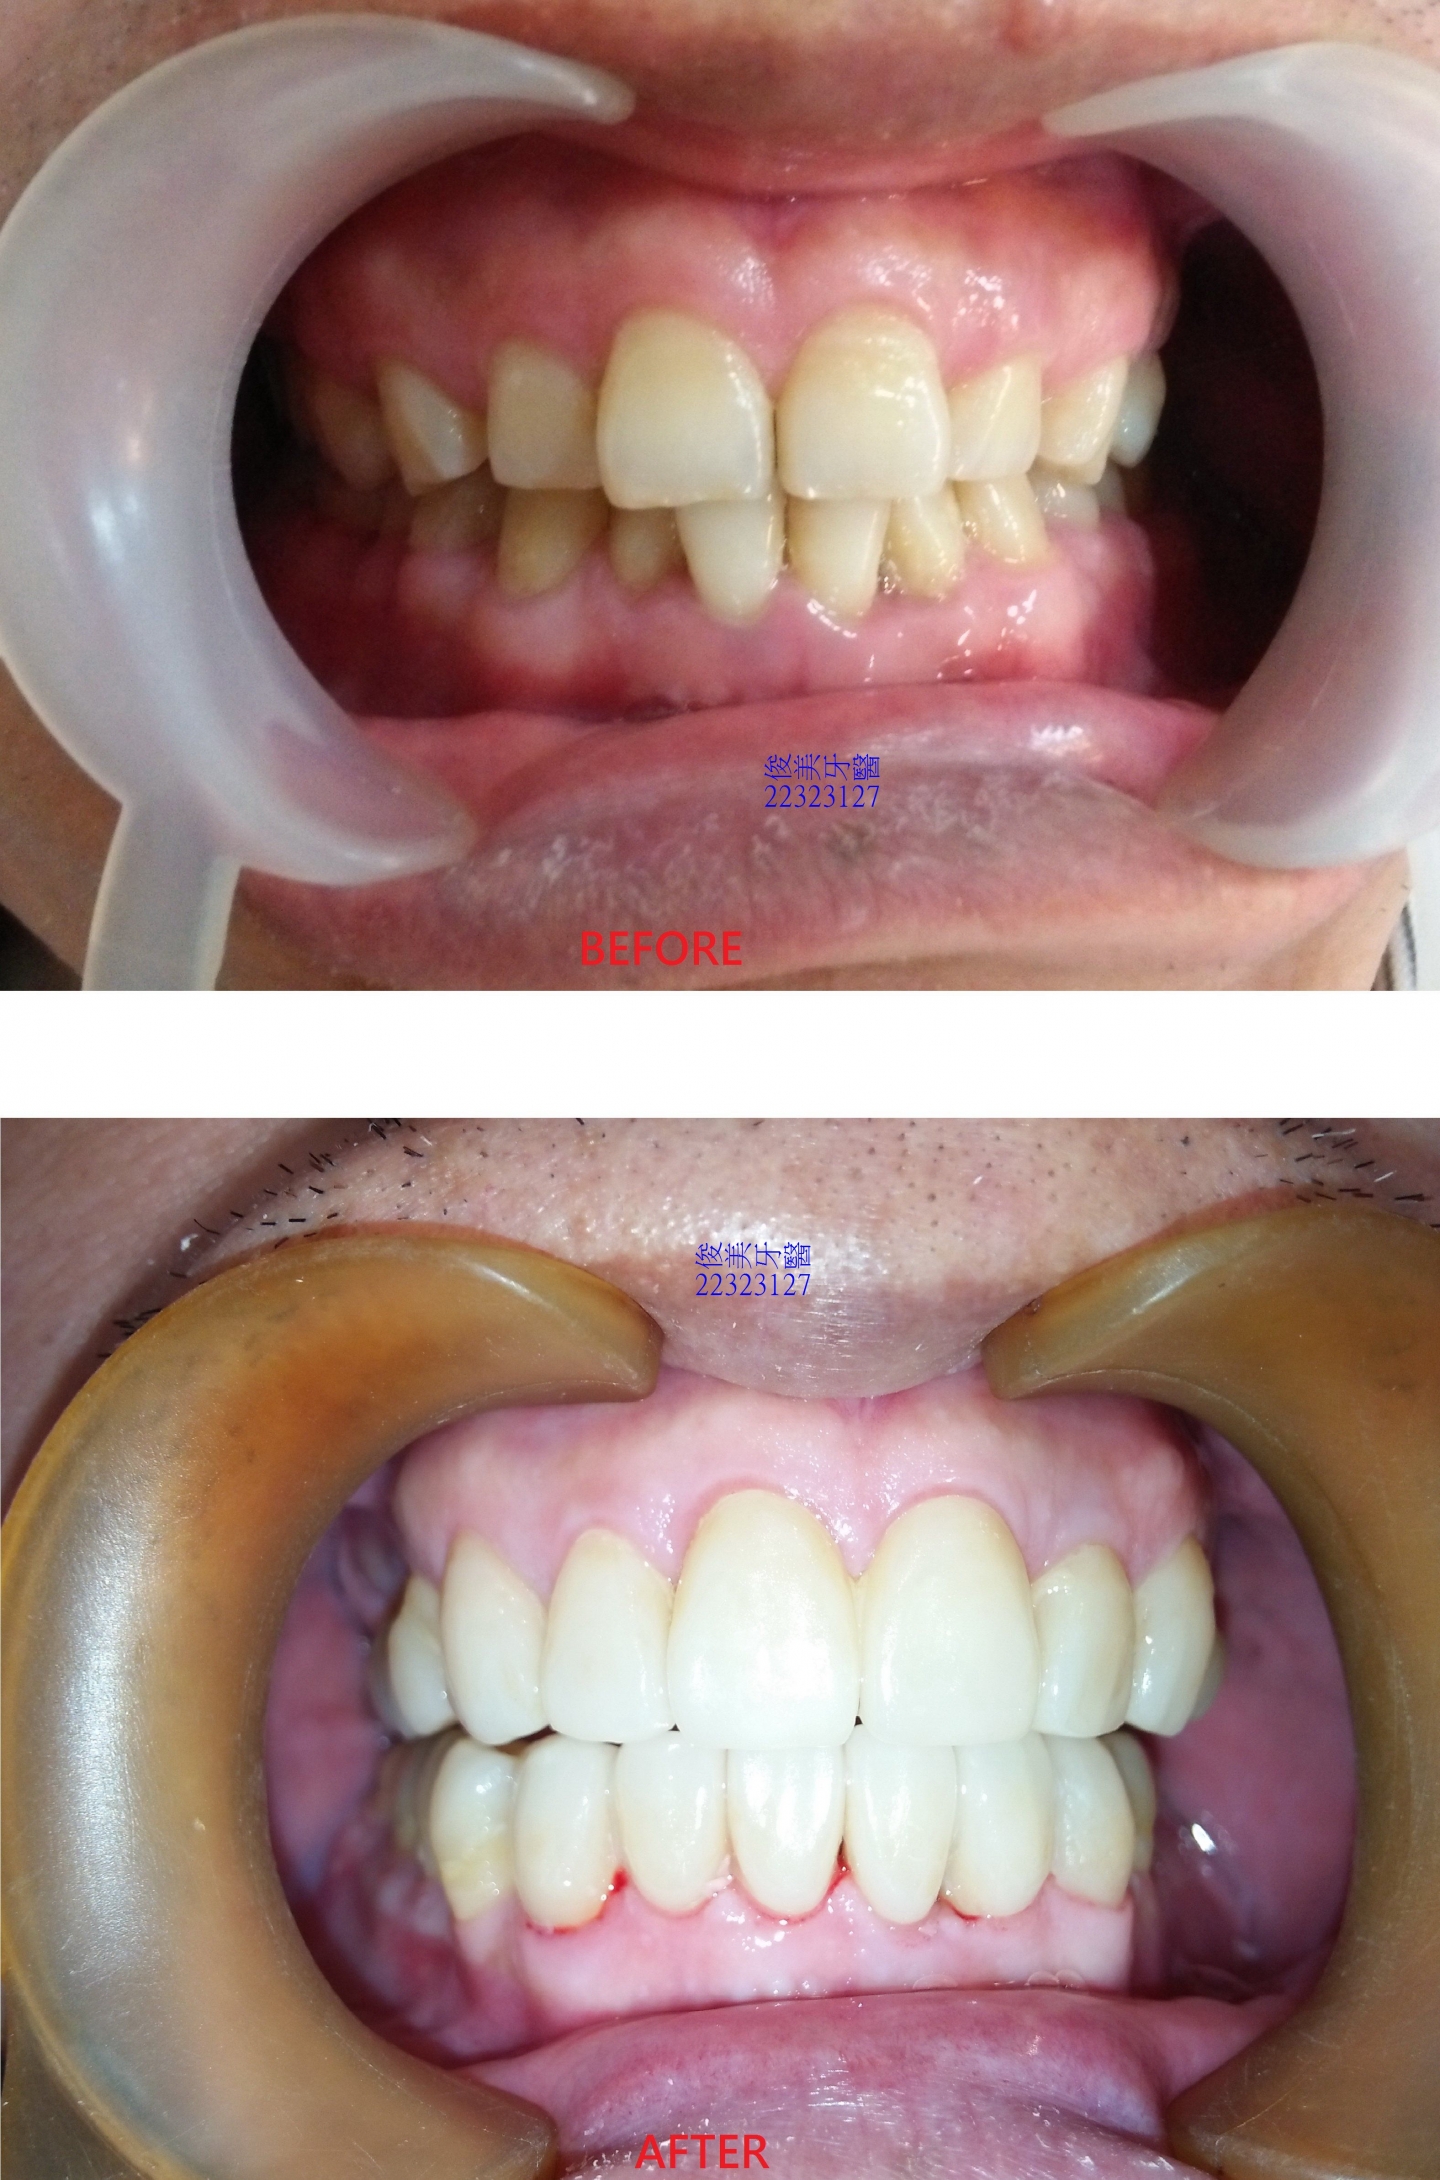

牙齒位移,前牙受力明顯過多,牙齒磨損的很平,牙齒變短、切端變厚。

牙縫開始變大。

後牙咬合高度逐漸變低。

後牙咬合高度逐漸變低;犬齒受力大,高度剩下2/3,切端皆已磨損喪失。

經過整合性治療......

利用矯正方式將患者的下顎牙弓擴張為原來的大小、恢復患者後牙喪失的高度,最後將前牙磨損的牙齒以

全瓷晶鑽貼片做修復,達到美觀的功能。

治療前、後,前牙差異比較。